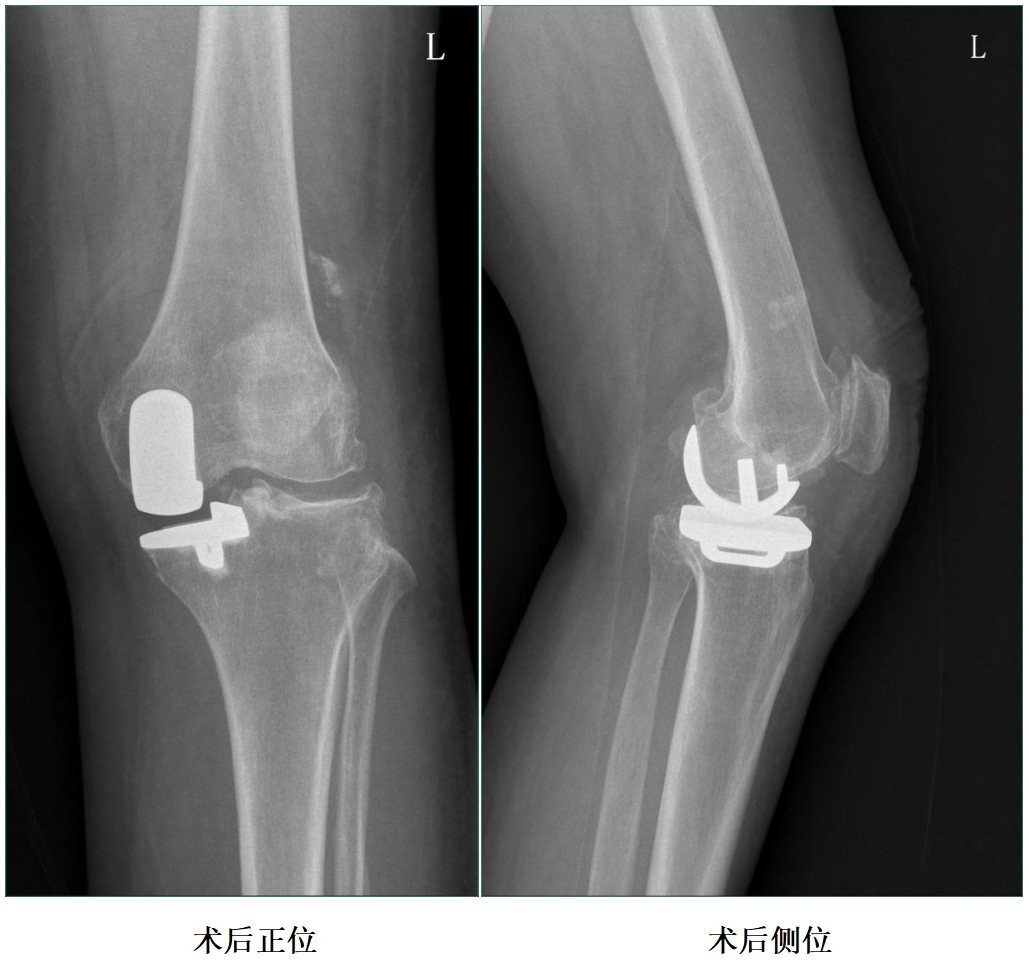

三、术后X片